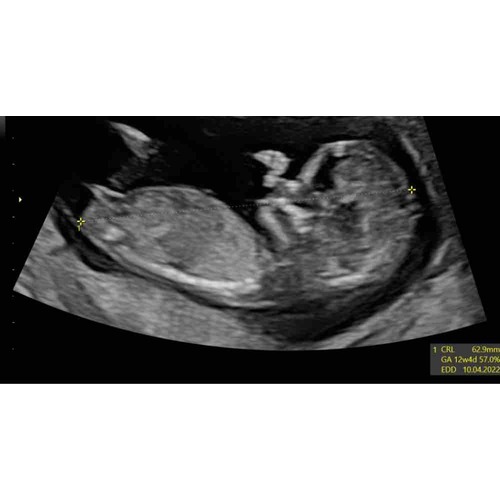

Zo leuk! Komt uit de niptest ook het geslacht naar voren dan? Ik heb het gister laten doen. Haha. Dit is mijn echo van afgelopen dinsdag 12+1 maar zie serieus zelf niks..

Ligt op z'n zij precies kan je moeilijk iets zien, had geen zin om op te foto te gaan denk ik hahah

Deze ook niet he?